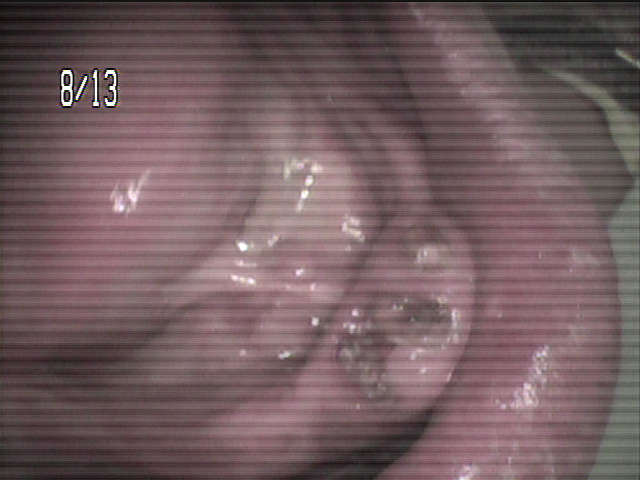

84歳女性のKさんは、下の顎が総入れ歯で、顎の状態が骨が少なく、

状態がよくないために、顎が入れ歯で痛くなりやすく、

コンフォート義歯を入れています。今回上の総入れ歯がやせてきてしまい、

新しく作製しました。上の顎の顎堤の状態は良好ではありませんが、

精密義歯で、いつでも顎の状態の変化に対応できる入れ歯を作製しました。

上の総入れ歯のコンフォート加工の症例です。 |